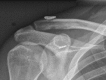

All-arthroscopic double-bundle coracoclavicular ligament reconstruction using autogenous semitendinosus graft: a new technique

We present our novel arthroscopic anatomic double-bundle coracoclavicular ligament reconstruction technique using a semitendinosus tendon autograft. The dorsal limb of the graft is positioned around the dorsal edge of the clavicle, re-creating the conoid ligament. The anterior limb proceeds superiorly and re-creates the trapezoid ligament. The solution effectively stabilizes the acromioclavicular joint and prevents anterior posterior translation. This new arthroscopic double-bundle coracoclavicular joint reconstruction is an effective and reliable method in stabilizing the clavicle and neutralizing the anterior-posterior translation, and we find it to be technically practical for the surgeon.